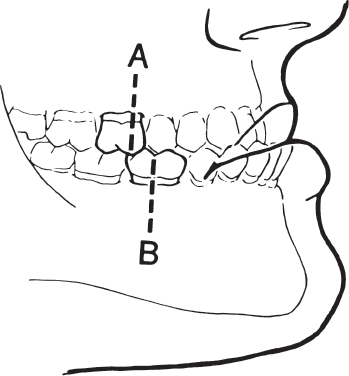

The class III malocclusion is primarily skeletally based. It is characterized by a large protrusive mandible or an underdeveloped, retrusive maxilla. The mesial buccal cusp of the first maxillary molar is positioned distal to its ideal position ( Fig. 70.5 ). Protrusion of the mandible is called prognathism.